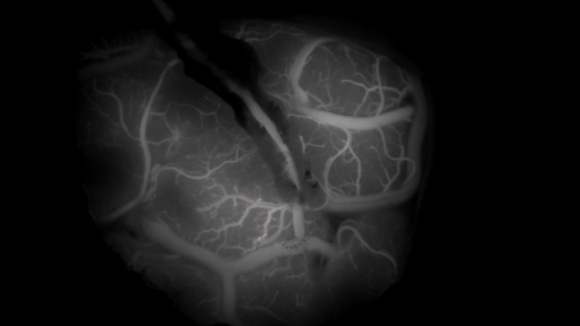

EBS '명의' 스틸컷. [사진=EBS]